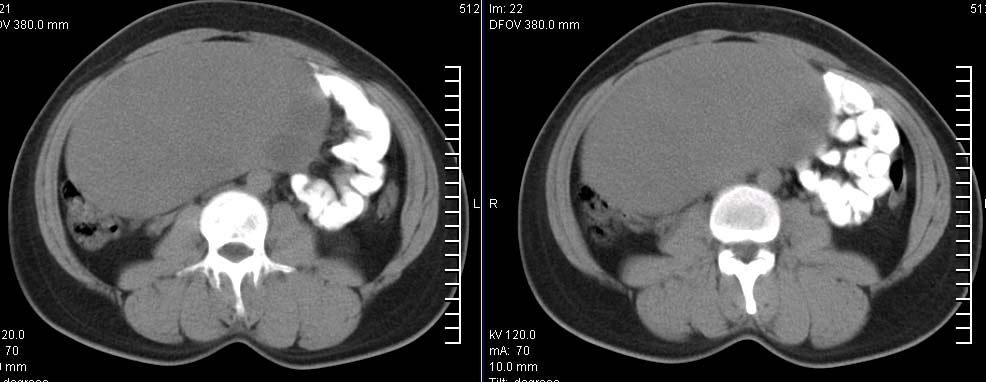

标题: CT9722:卵巢巨大占位,约10*18*21CM大小

卵巢巨大占位,约10*18*21cm大小

卵巢囊腺瘤可能性大.可见低密度

考虑:右侧卵巢囊性瘤可能性大 建议增强扫描。

肿瘤的密度有点高.和子宫差不多?且和子宫相连呢?我考虑来源于子宫,子宫巨大子宫肌瘤可能性大!(局部有坏死?)

右侧卵巢囊性瘤可能性大 ,5楼,密度不一样,是窗调得太宽

囊腺瘤不管是浆液性,还是黏液性的,液体成分应该占的比例很大吧!!这个病灶其实是个实性肿块,更看不到囊腺瘤所能见到的分隔??请笔者提供ct值?望大家再仔细分析??

右侧附件区巨大囊性肿块,边缘光滑,密度较高,左侧缘由多个低密度区,首先考虑囊腺瘤可能。